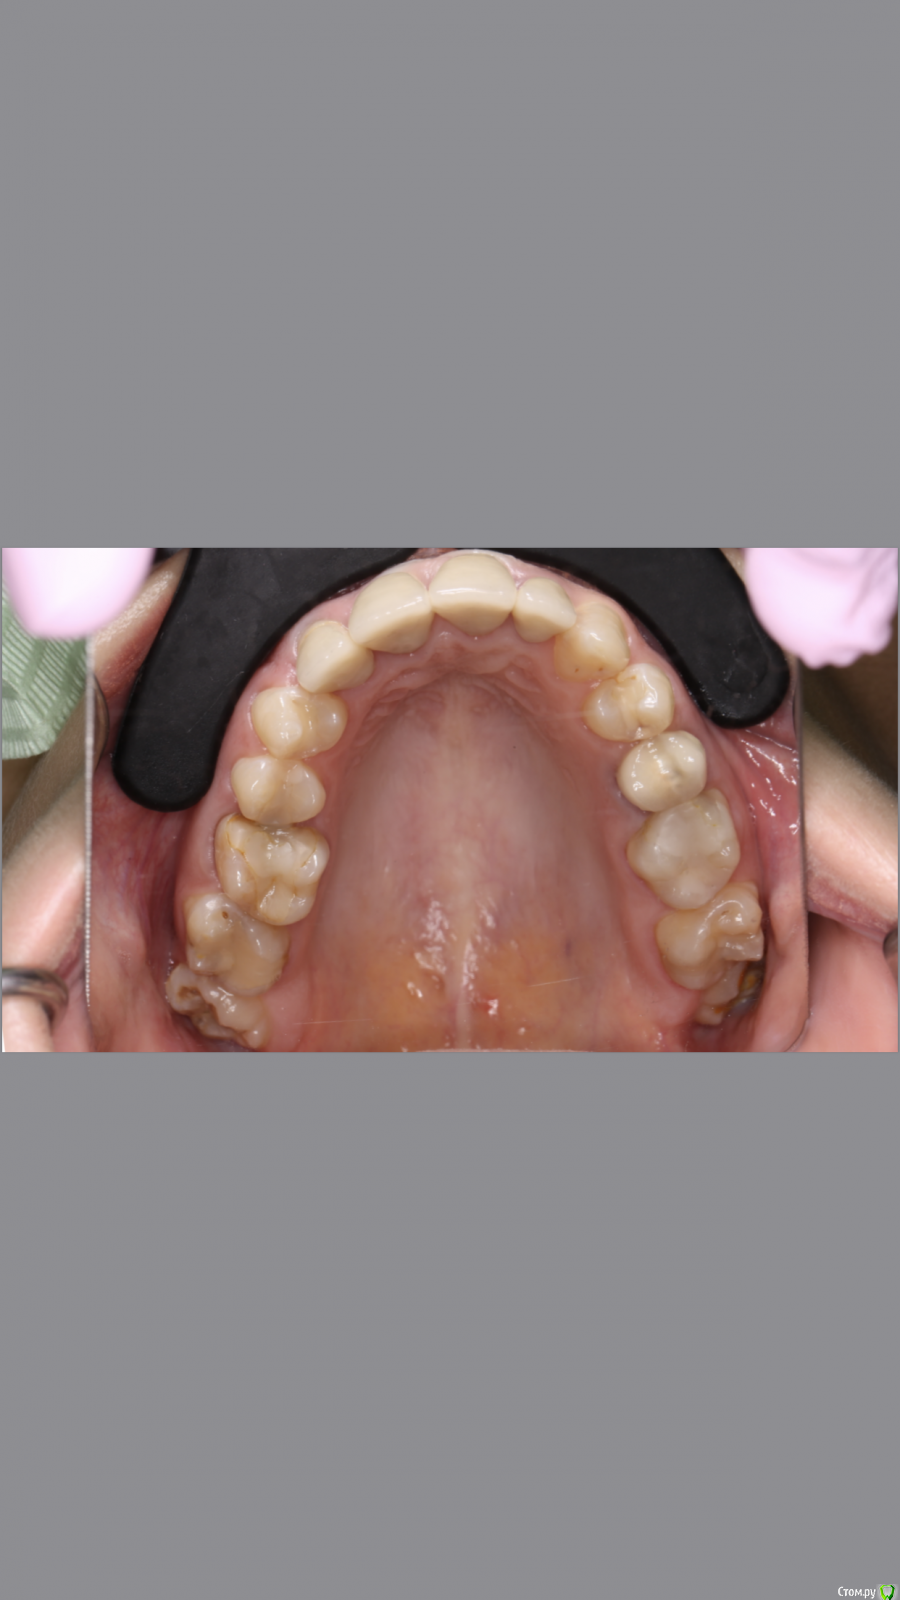

dr.Dre Опубликовано 8 июня, 2019 Поделиться Опубликовано 8 июня, 2019 Добрый вечер.Коллеги помогите грамотно скласть план лечения?С чего начинать ,терапия,ортодонтия ортопедия Ссылка на комментарий

Monkey Опубликовано 19 июня, 2019 Поделиться Опубликовано 19 июня, 2019 Добрый вечер.Коллеги помогите грамотно скласть план лечения?С чего начинать ,терапия,ортодонтия ортопедияСанация, удаление 8-х, ортодонтическое лечение с раскрытием места 36,23 (заодно и среднюю линию откорректируете), протезирование Ссылка на комментарий